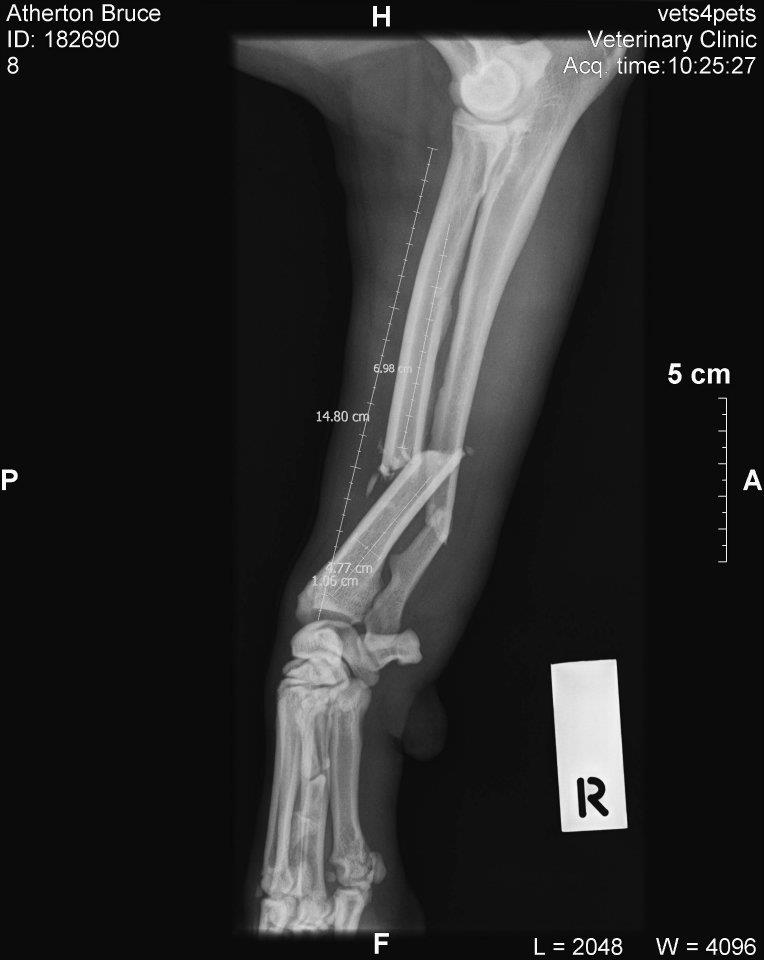

July was the first and only time the dogs have been out the front gate, the results of which was a broken Bruce. I’d left the front gate open for Linhda, again for the first time and something I’ve never done since, and then forgotten and let the dogs out the front to pee before bed. It wasn’t five minutes later that I realised, but they were already out. I found them a kilometre or so down the road. Domino and Tatyl jumped in the car, but Bruce wouldn’t come close. I figured he knew he was in trouble and so was staying back. I let him run home besides the car, and on the way home noticed he was limping. Then I realised he wasn’t using his right front let at all. Then I saw that it was actually dangling in the breeze and pissing out blood.

Freshly broken Bruce.

Bruce feeling pitiful.

A midnight trip to the emergency vet room, followed by some work by an orthopaedic surgeon, resulted in a plate and 9 screws holding together his broken ulna and radius.

Broken ulna and radius.